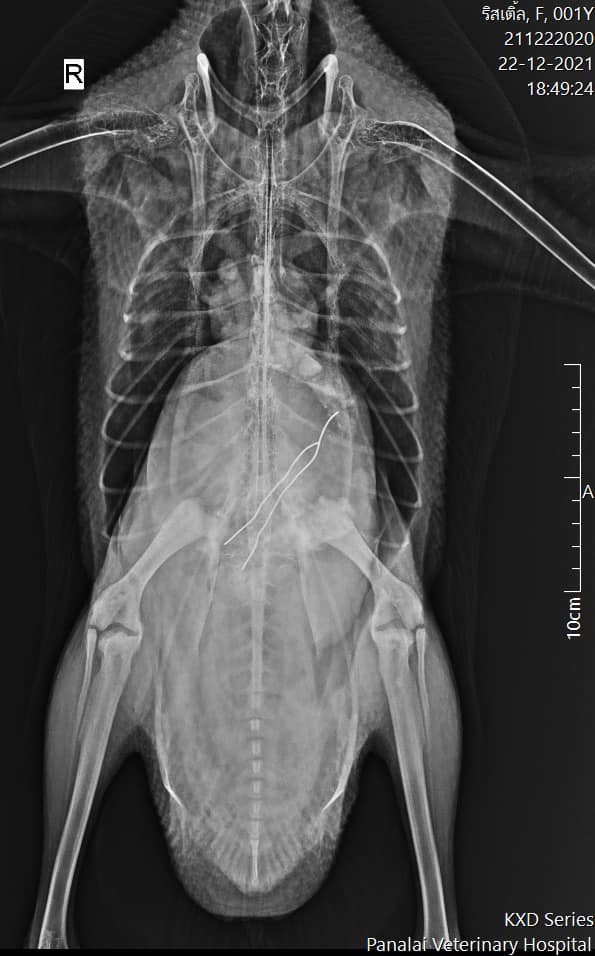

位於泰國暖武里府Tiwanon的動物醫院Panalai Veterinary Hospital,日前收治了一隻誤把電線吞下肚的白鵝,當時這隻貪吃P孩鵝已經完成鎮定麻醉,長脖子靠著枕頭、翅膀展開和雙腳伸直,乖乖躺在病床上了,而牠的腹部為了方便手術,也已先完成剃毛露出粉色的皮膚www